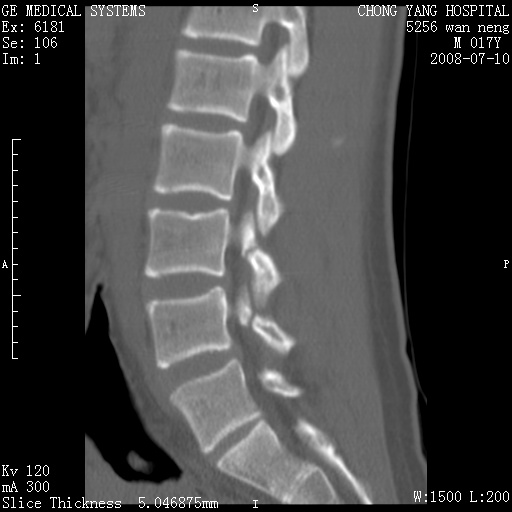

腰3、4椎弓崩裂

腰3、4椎弓不连

支持:腰3、4椎弓峡部崩裂。

腰3、4椎弓峡部不连

支持:腰3、4椎弓峡部崩解。

腰3、4,如受过外伤则为陈旧骨折,否则为骨质不连

图片漂亮,目前也只能看到腰3、4骨质不连

腰3、4椎弓峡部裂。

腰3、4椎弓峡部裂。支持

重建图像见多个椎弓峡部不连(不足为据),平扫未见异常。

支持腰3、4椎弓峡部崩裂。